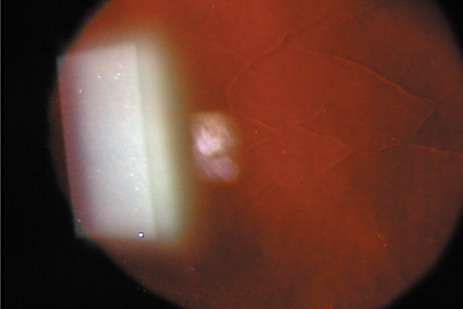

In 1983, Trokel and coworkers first reported the precise and controlled etching of the cornea by an argon–fluorine (ArF) excimer laser.28 Puliafito and colleagues compared the histopathologic effects of linear cornea ablation at 193 and 248 nm.29 Both studies found excellent preservation of normal corneal stromal microstructure adjacent to the ablation zone at 193 nm (Fig. 1). The adjacent cornea remained optically clear. High-power transmission electron microscopy showed a submicron zone of electron density immediately adjacent to the ablation only. Kerr-Muir and associates first described a pseudomembrane that appears to seal cells and cellular nuclei transected by the laser beam.30 In contrast, at 248 nm, disorganization of the collagen microstructure extended into the adjacent stroma for more than 10 νm.29 The cornea immediately adjacent to the ablation showed a loss of transparency, which was indicative of thermal injury. Further, a study by Peyman and associates31 showed a significant coagulative effect from 308-nm excimer laser radiation with induced corneal necrosis, stromal opacification, and endothelial cell damage.

Fig. 1. Light micrograph of a 193-nm, slit-like ablation in a bovine cornea. Dosage parameters: 20,000 pulses, 50 Hz, 125 mJ/cm2 per pulse, with a 10 νm mask (original magnification ×214). (Puliafito CA, Steinert RF, Deutsch TF, et al: Excimer laser ablation of the cornea and lens: Experimental studies. Ophthalmology 92:741, 1985)